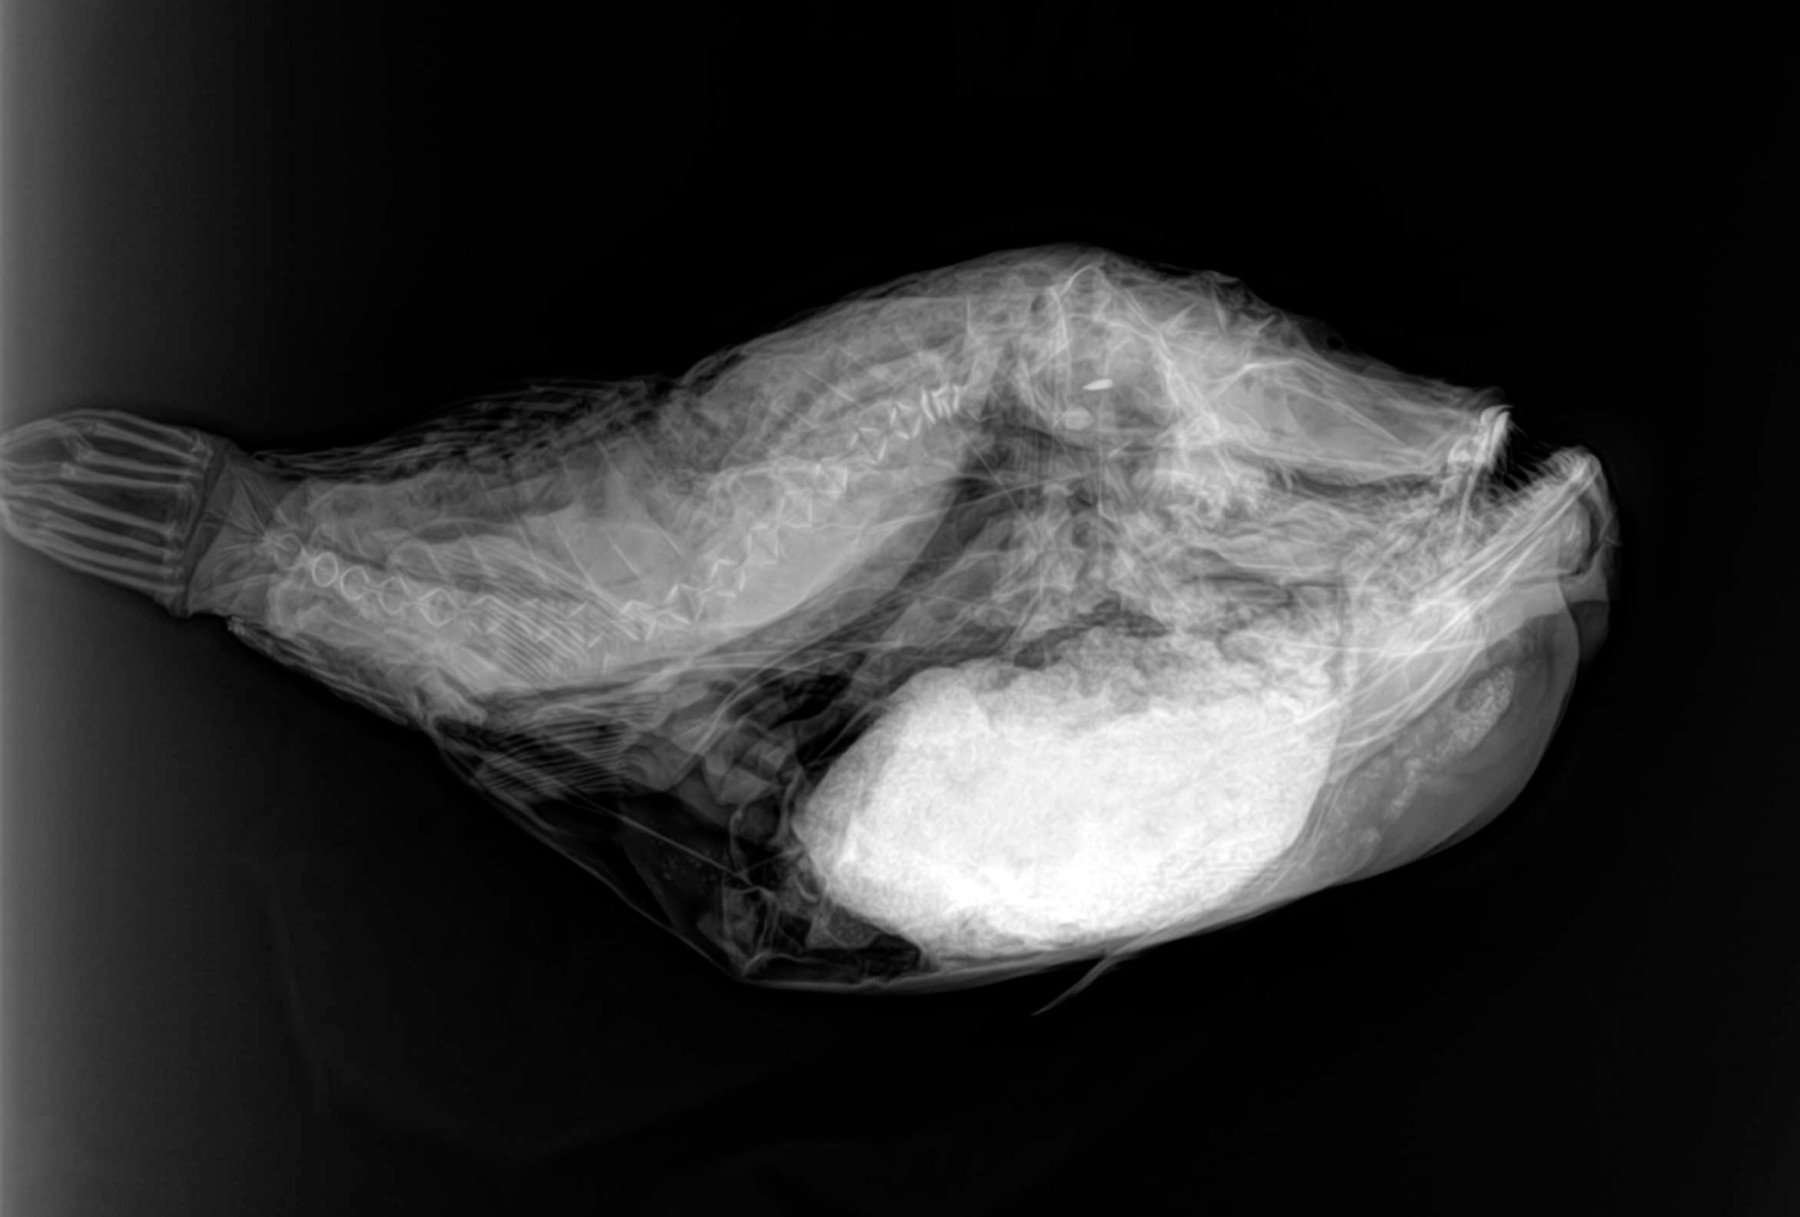

Cambios Térmicos en las Extremidades de Caballos,

Asociados a Golpes y su Evaluación por Termografía.

Los caballos de salto, en competencia, pueden derribar obstáculos y lastimarse. Si se golpean, no siempre claudican. Considerando al calor como un signo de inflamación, se evaluaron los cambios térmicos de 6 áreas de las extremidades torácicas y pelvianas de 23 caballos de salto en nivel de competencia de 1.05 a 1.60 m de altura, por medio de termografía durante 4 días de competencia (N=2208 áreas).